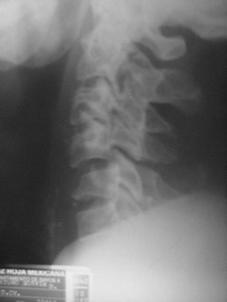

TRAUMA CERVICALA

Incidenta oblica Incidenta laterala Incidenta antero-posterioara

Aspect normal Aspect normal Aspect normal

Fractura de odontoida si fractura-luxatie atlanto-axiala Fractura-luxatie C5 - C6

Fractura-luxatie C5 - C6 Fractura cominutiva C4

Fractura-luxatie C7 - T1